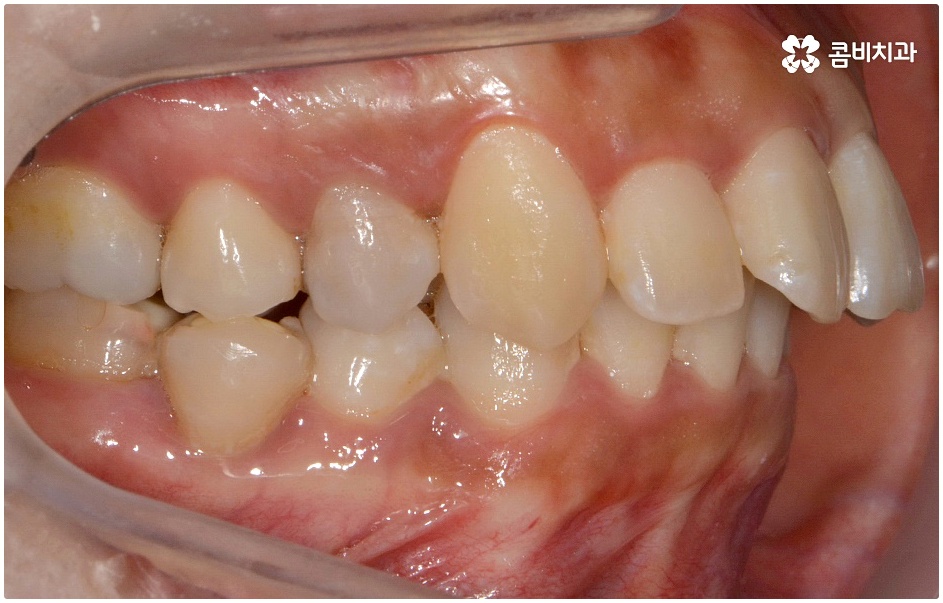

돌출입의 경우 씹기가 불편하고 입을 닫을 때 어려움이 있으며 웃을 때 부자연스러운 입 모양 및 코보다 입이 더 튀어나와 균형이 맞지 않는 옆모습에 대한 심미적인 불만족을 이유로 돌출치아교정 을 고려해 볼 수 있는데요.

돌출입에는 두 가지 경우가 있는데 먼저 치아들의 각도가 앞으로 뻗어서 돌출되는 경우와 골격 구조상 튀어나온 경우 (즉, 치아를 잡아주는 상악 치조골, 잇몸 자체가 돌출된 경우 또는 하악 턱이 뒤로 후퇴한 경우) 이렇게 나눌 수 있으며 정확한 원인을 파악하는 것이 중요하기 때문에 꼼꼼한 검진 및 면밀한 상담이 우선시 될 필요가 있어요.